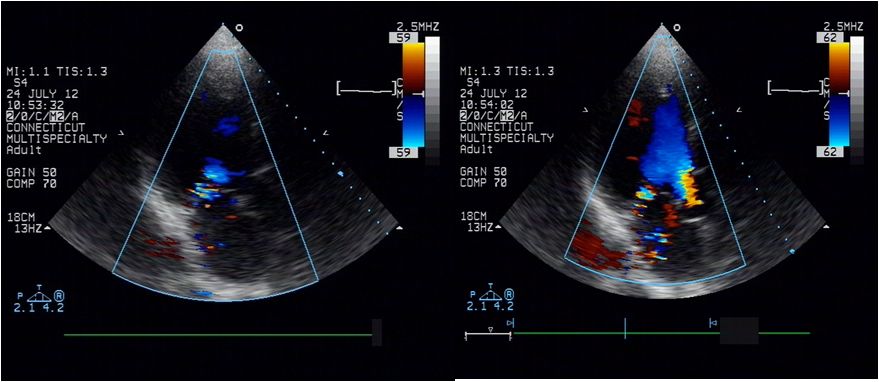

➤ 全心扩大(左房内径48mm,左室内径(d)70mm,(s)53mm)

➤ LVEF48%,肺动脉压80mmHg

➤ 二尖瓣前叶收缩期突向左房,二尖瓣收缩期见中-重度关闭不全

➤ 室间隔厚11mm,左室后壁厚11mm